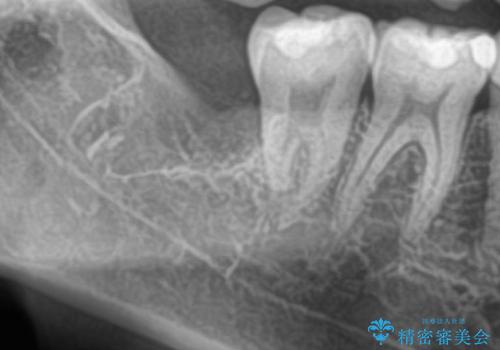

- 当院でセラミック治療を行い、その後に親知らずを抜きたいとのことで来院された患者様です。

CTで神経の位置などを確認し、抜歯術を行いました。

一週間後に抜糸を行いました。